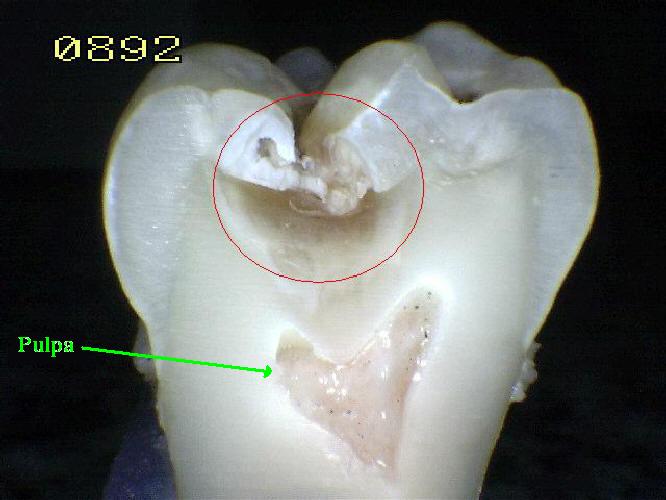

La

Pulpa dental es un órgano junto con la

dentina altamente organizado. (Órgano dentno

pulapar)

Con funciones:

-

de reparación, como es la

producción de dentina secundaria.[14]

-

Metabólicas e

inmunitasrias [22]

-

A lo largo del borde

entre la dentina y la pulpa hay células en

empalizada llamada odontoblastos, que

inician la formación de dentina. [21

-

Su estructura principal

son fibroblastos con una red proteica de

fibrina laxa y vascular arteriovenosa con

fibras nerviosas desmielinizadas

sensitivas.[14]

. La pulpa se llama

comúnmente "el nervio" del diente.